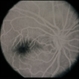

- Ocular ischaemic syndrome

- ocular ischemic syndrome

- Imaging device

- Fundus camera

- Ocular ischaemic syndrome, left eye - fluorescein angiogram, late phase.